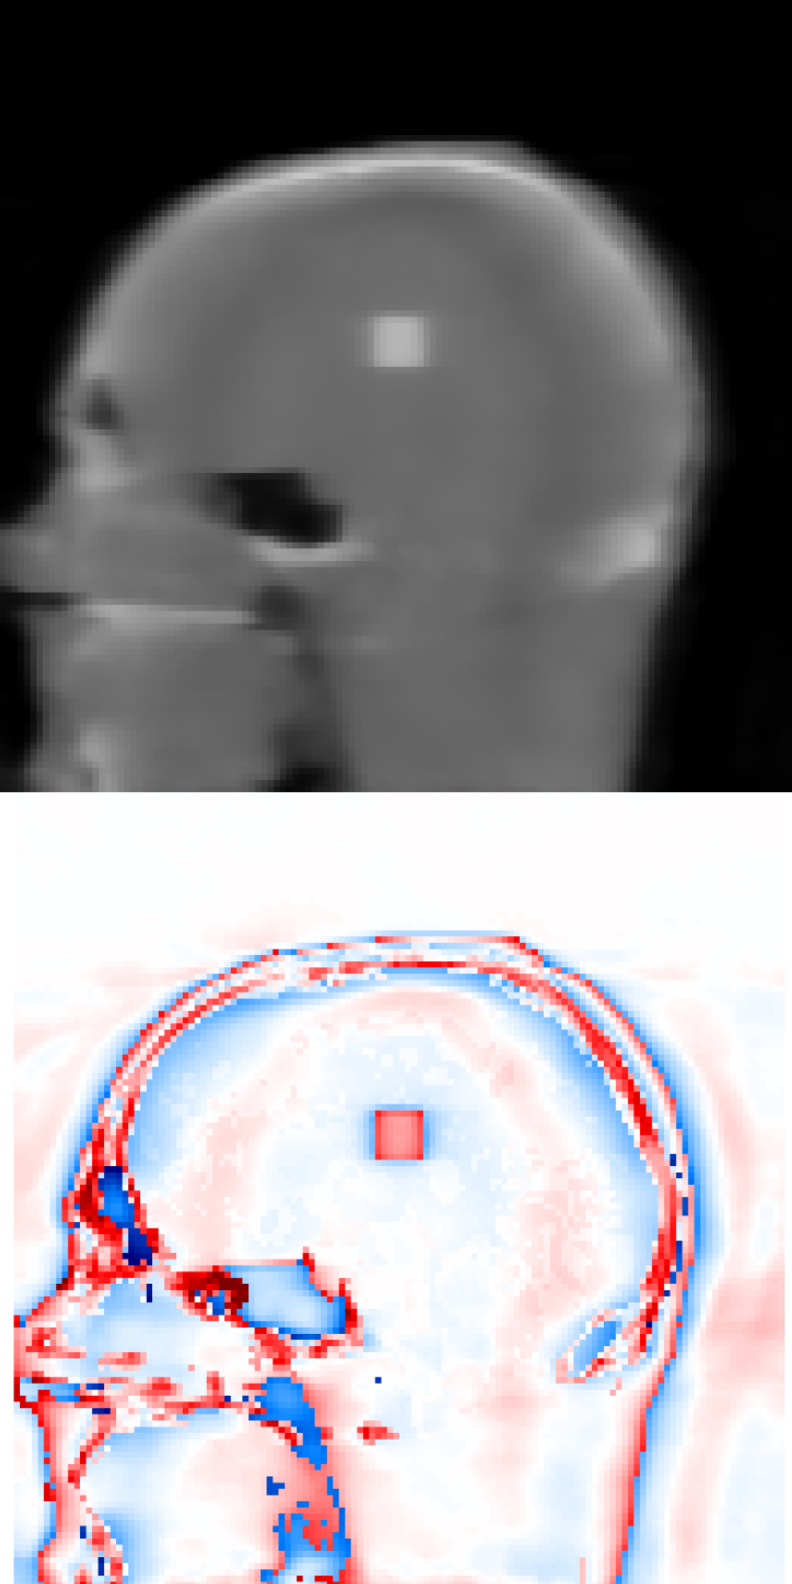

Figure 1 exhibits a slice of the reconstructed images using all the aforementioned algorithms. Here, (a) is the prior image 𝒙p\boldsymbol{x}_{p}, (f) is the ground truth, and the rests are the reconstructed images (top) with the corresponding reconstructions errors (bottom), all displayed using the same colorbar. Note that the error is just the difference between the reconstruction with respect to the ground truth image, so that high pixel intensity indicates inaccurate reconstructions and a fully black image would indicate a perfect reconstruction. This local error information is more informative than only displaying the error norms, or global error, since one can easily observe there is a high local difference between reconstructions.

Since this is a very undersampled dataset, FDK performs qualitatively poorly. Also for SIRT, and IRN-TV the quality drops significantly. The ASD-POCS-TV and ASD-POCS-PICCS are performing well, although a lot of texture information from the image is lost due to the smoothing process. However, the reconstruction time is higher than the other algorithms. The proposed algorithms perform better considering the available texture detail and the reconstruction time. Especially, the image in figure 1(h), IRN-PIPLE, is reconstructing the tumour better by preserving the texture information. Moreover, in figure 1(i), the tumour is more prominently visible due to the added TV regularization in the IRN-PICCS algorithm, however, with compromised original texture information of the image. Note that, for both proposed algorithms, the reconstruction time is in the range of 13 to 76 seconds only.

Figure 1: Reconstructed images using the digital head phantom data, with heavily undersampled projections (20 angles per set). The reconstructed images are shown in [0, 1]; difference images in [–0.5, 0.5].